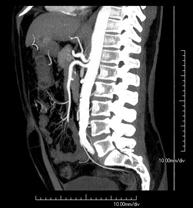

Prova diagnòstica no invasiva que consisteix en l'estudi de l'artèria aorta abdominal a través de l'obtenció d'imatges d'alta definició anatòmica mitjançant l'ús d'un equip de TC (Tomografia Computeritzada) i de contrast iodat. La qualitat de les imatges permet realitzar reconstruccions en 2D i 3D gràcies a estacions de treball especialitzades en l'estudi arterial. Està indicat en aquells pacients amb malaltia vascular (arteriosclerosi), en aneurismes d'aorta, en pacients amb dolor abdominal de possible origen vascular, en estudis prequirúrgics de lesions adjacents a l'aorta abdominal com a "mapa" vascular. La informació obtinguda de manera no invasiva és indispensable per als pacients que requereixen tractament percutani o quirúrgic. En aquells pacients que només requereixen seguiment de les lesions vasculars, aquesta tècnica és la tècnica no invasiva d'elecció juntament amb l'angio-RM. - Angio-TC Artèries renals

Prova diagnòstica no invasiva que consisteix en l'estudi de l'artèria aorta abdominal amb l'obtenció d'imatges d'alta definició anatòmica mitjançant l'ús d'un equip de TC (Tomografia Computaritzada) i contrast iodat. La qualitat de les imatges permet realitzar reconstruccions en 2D i 3D gràcies a estacions de treball especialitzades en l'estudi arterial. Està indicat en aquells pacients que pateixen malaltia vascular (arteriosclerosi), aneurismes d'aorta, en pacient amb dolor abdominal d'un possible origen vascular, en estudis prequirúrgics de lesions adjacents a l'aorta abdominal com el "mapa" vascular, etc. La informació obtinguda de forma no invasiva és indispensable per als pacients que requereixen tractament percutani o quirúrgic. En aquells pacients que només requereixen un seguiment de les lesions vasculars, aquesta tècnica és la tècnica no invasiva d'elecció juntament amb l'angio RM. - Angio TC d'artèries renals